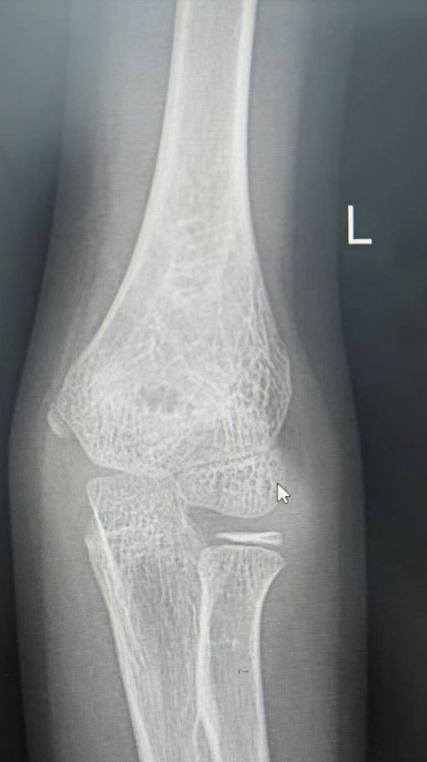

如5岁男童瑞瑞踩着平衡车从广场边缘台阶上摔下,导致左臂肱骨髁上骨折;6岁女童萱萱骑滑板车避让障碍物失去平衡,重重摔倒,造成胫骨骨折。

桡骨远端骨折,通过手法复位